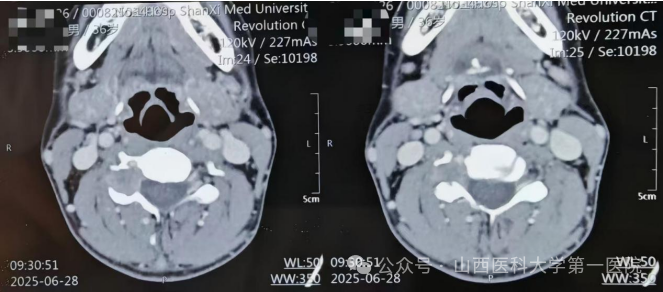

36岁男性患者,诊断为颈椎肿瘤,影像学检查分析该肿瘤位于颈4椎板处,内侧紧贴脊髓神经,前方与椎动脉紧密贴合,已就诊于多家医院,被告知该疾病非常罕见,手术难度极高、风险极大。

患者了解到山医大一院成立了张西峰工作室后,再次燃起希望。经张西峰脊柱团队术前仔细评估,认为手术应最大限度保护患者的神经和血管,可以在微创且局麻条件下完成该肿瘤的切除。张西峰主刀在局麻患者完全苏醒的状态下,完成该颈椎肿瘤切除,历经约90分钟,患者术后立即下地行走,感觉四肢活动完全正常。